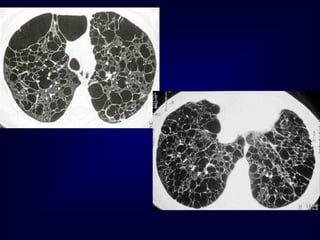

A professional diver..........

.......after cessation of smoki